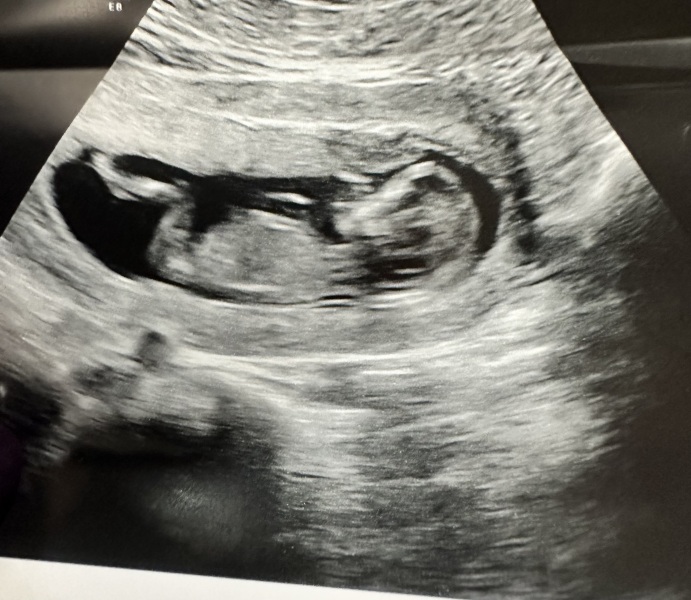

To start with, I am just happy to have seen a healthy baby on my 12+4 week scan.

Everyone seems to be giving me options on the gender. I can only use the skull theory because no nub was visible.

In one photo mine looks 'blocky' and in others very round. Because it was moving around so much, who knows 😂

@Lithgow2000 as you’ve seen the shape on the skull on the picture changes as the sonogram moves. Nub theory can be accurate but only if you have a clear image and know what you’re looking at. All the other theories and old wives tales are just nonsense. Some will swear they’re true but it’s 50/50 guesswork

Any thoughts about our 12+3 skull?! X

After all my research i found the skull theory is really really inaccurate and basically just depends on the angle. Blocky skulls have been girls and round skulls have been boys 😂 if you have a nub shot that's supposed to be really accurate